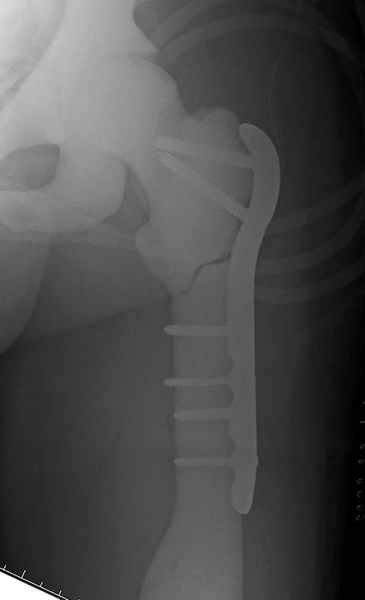

Здесь у меня дополнительные снимки с большим разрешением и в разных режимах, а то те дигитал снимки совсем очень блеклые, может, эти изображени изменят выбор тактики

После неудачной попытки скелетного вытяжения в первом мед.учреждении, после осмотра снимков и изучения истории, поставили диагноз “Остеопетроз” или мраморная болезнь, редкая наследственная костная паталогия, где имеется нарушение формации остеокластов.

Конечно, было бы идеальным применение интрамедуллярного остеосинтеза, но учитывая прежний собственный опыт (лечил перелом бедра) и

публикации, предупреждающие о трудностях при обработке кости (иногда из-за неподготовленности инструментария результатом была неадекватная фиксация перелома, или перенос операции из-за фактора усталости оперирующего персонала), решили применить пластину (и в этом же случае был выбран Synthes plate, так что представитель за два дня

зароботал... на десерт тоже).

Заказаны были дополнительные различные дрели, и на следующий день, усиленной бригадой, больного прооперировали, потратив на каждое отверстие около 25-35 минут, хотя сверлили с охлаждением по нарастающей по диаметру сверл и с их заменой каждые 2 мм сверления.

Теперь стоит задача со сращением перелома, из-за отсутствия литературных данных по применению костных стимуляторов при остеопетрозе, и не зная как поведет в этой среде Grafton, все таки надеюсь, что даст толчок к стимуляцию, решил применить пастообразную деминерализованную костную матрицу, расположив спереди между отломками.